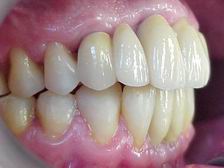

Prova da cerâmica sem glaze VISTA LATERAL DIREITA

Aspecto final após glazeamento da cerâmica e remoção do aparelho ortodôntico